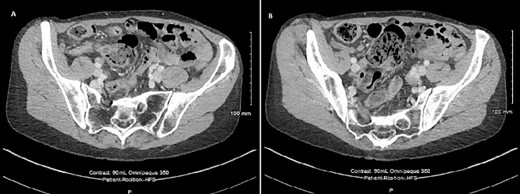

Microscopically (Fig. 3), sections of base of appendix and adjacent caecum showed a submucosal cystic lesion lined by large bowel mucosa with mucosal lymphoid follicle resembling appendiceal lining, in keeping with an appendiceal diverticulum at the base of appendix resembling a submucosal caecal lesion. Sections of the rest of appendix showed slight dilatation of the lumen with mildly inflamed mucosa, but were otherwise unremarkable. There was no evidence of dysplasia or malignancy.

Microscopic section showing appendiceal diverticulum, Arrow: Caecal mucosa, Arrowheads: Submucosal lesion.